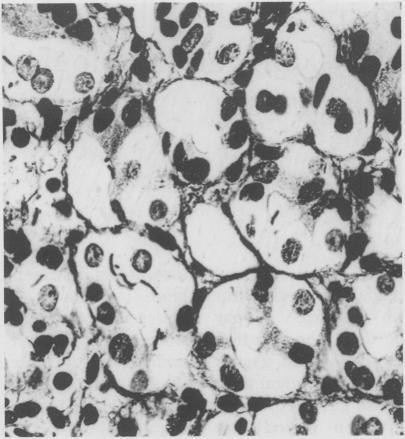

An intensive histological search for Helicobacter pylori in gastric biopsy specimens has led to the detection of other spiral shaped bacteria in the human gastric mucosa. The clinical and morphological findings of 39 cases (0.25% of all gastric biopsies performed in the observation period) are reported for 34 patients (87.2%) complaining of upper abdominal discomfort. Five patients (12.8%) had chronic gastritis and 34 (87.2%) chronic active gastritis. The organisms were seen by light microscopy deep in the gastric foveolae and intracellularly. The scanning and transmission electron microscopic findings show bacteria which invade and damage gastric mucosal cells. These organisms are similar to the spiral shaped bacteria found in the stomachs of cats and dogs and non-human primates. In eight patients organisms were not detected after four weeks of treatment with bismuth salts. The disappearance of the organisms coincided with resolution of the chronic active gastritis and the symptoms.

在胃活检标本中对幽门螺杆菌进行密集的组织学检查时,发现了人类胃黏膜中的其他螺旋形细菌。报告了34例(87.2%)主诉上腹部不适患者的临床和形态学结果(占观察期内所有胃活检的0.25%)。5例(12.8%)患有慢性胃炎,34例(87.2%)患有慢性活动性胃炎。这些微生物在胃小凹深部和细胞内通过光学显微镜可见。扫描和透射电子显微镜检查结果显示,这些细菌会侵入并损害胃黏膜细胞。这些微生物与在猫、狗和非人类灵长类动物胃中发现的螺旋形细菌相似。8例患者在使用铋盐治疗四周后未检测到微生物。微生物的消失与慢性活动性胃炎及症状的缓解同时出现。